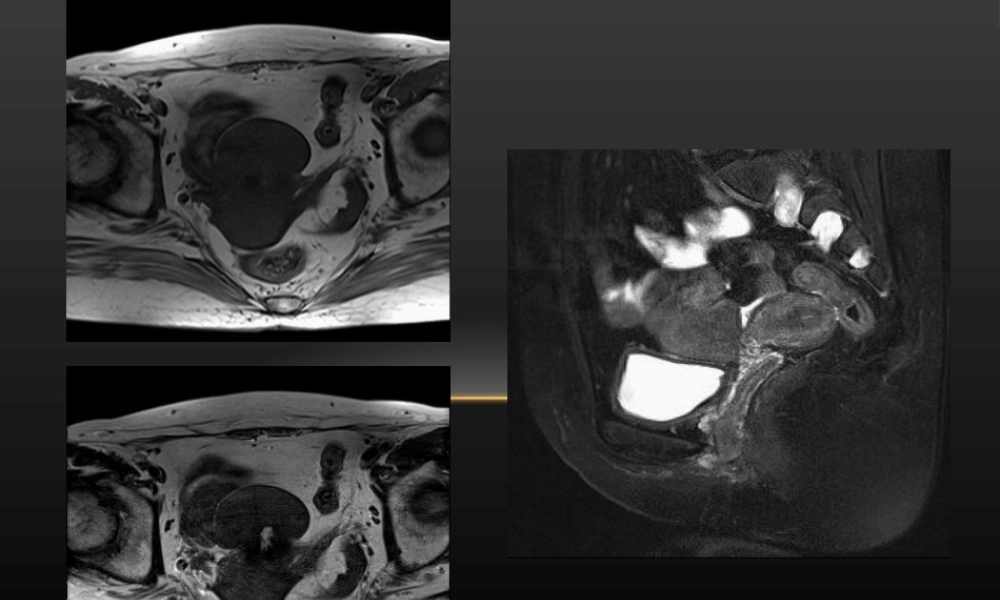

第一页,共二十一页。第一页,共二十一页。UterineMalformations子宫畸形第二页,共二十一页。第二页,共二十一页。病因及病症•病因:子宫、宫颈及阴道上段是胚胎时期双侧副中肾管融合发育而成,先天性子宫畸形是由于副中肾管在胚胎发育过程中受各种因素影响,发育停滞在不同阶段形成的。•主要病症•月经异常•不孕•病理妊娠第三页,共二十一页。第三页,共二十一页。分类•子宫未发育或发育不良•先天性无子宫〔congenitalabsenceofuterus〕:因双侧副中肾管形成子宫段未融合,退化。常合并无阴道。•始基子宫〔primordialuterus〕:始基子宫为双侧副中肾管融合不久即停止发育,子宫极小,多数无宫腔或为一个实性肌性子宫,偶可见始基子宫有宫腔和内膜。•幼稚子宫〔infantileuterus〕:为双侧副中肾管融合形成子宫后停止发育所致,子宫体较小,可有宫腔和内膜。第四页,共二十一页。第四页,共二十一页。第五页,共二十一页。第五页,共二十一页。•单角子宫与残角子宫•单角子宫〔unicornousuterus〕:仅一侧副中肾管正常发育形成单角子宫,另一侧副中肾管完全未发育或为形成管道,未发育侧卵巢、输卵管和肾脏往往同时却如。•残角子宫:一侧副中肾管中下段发育缺陷,形成残角子宫,残角子宫侧有正常的卵巢及输卵管,常伴有同侧泌尿系器官发育异常。常与单角子宫同时存在,一侧副中肾管发育为单角子宫,另一侧副中肾管中下段发育缺陷,形成残角子宫。第六页,共二十一页。第六页,共二十一页。第七页,共二十一页。第七页,共二十一页。•双子宫〔didelphicuterus〕为两侧副中肾管未融合,各自发育形成两个单角子宫和两个宫颈,两个宫颈可分开或相连,宫颈间也可有交通管,也可为一侧宫颈发育不良、缺如,双子宫可伴有阴道纵隔或斜隔。第八页,共二十一页。第八页,共二十一页。•双角子宫〔bicornuateuterus〕是双侧副中肾管融合不良所致,分为完全性双角子宫〔从宫颈内口处分开〕,不全性双角子宫〔宫颈内口以上处分开〕。第九页,共二十一页。第九页,共二十一页。•纵隔子宫为双侧副中肾管融合后,纵隔吸收受阻所致,临床可分为:完全纵隔子宫〔纵隔由宫底至宫颈内口之下〕和不全纵隔〔纵隔终止于宫颈内口之上〕。第十页,共二十一页。第十页,共二十一页。•弓形子宫为宫底部发育不良,宫底中间凹陷,宫壁略凸向宫腔。第十一页,共二十一页。第十一页,共二十一页。第十二页,共二十一页。第十二页,共二十一页。第十三页,共二十一页。...